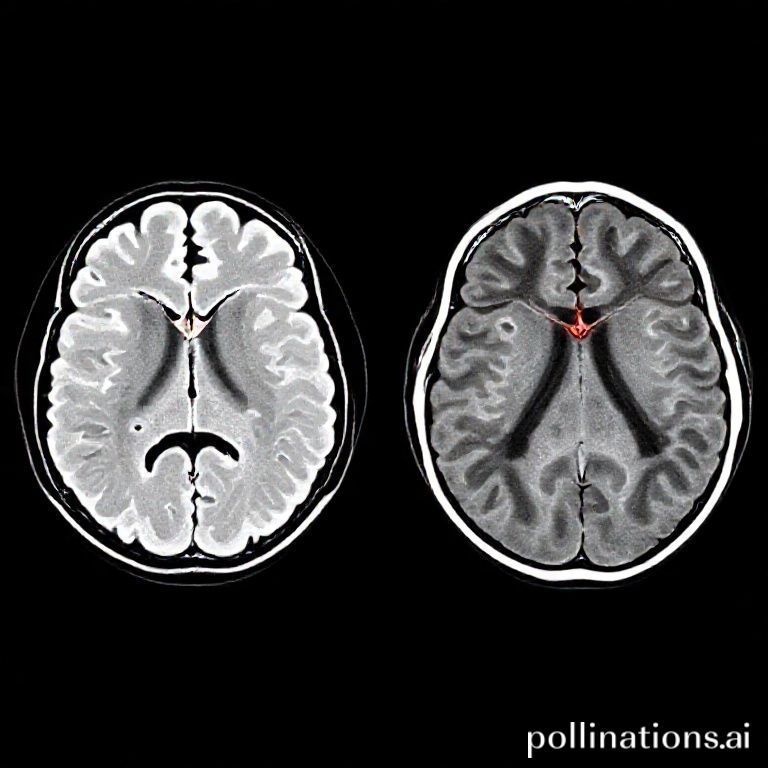

정밀 영상 진단: MRI, 더 깊이 들여다보기

CT가 급성 뇌출혈 진단에 '빠르고 명확한' 역할을 한다면, MRI(Magnetic Resonance Imaging)는 뇌의 미세한 변화까지 '정밀하게' 들여다볼 수 있는 진단법이에요. MRI는 강력한 자기장과 고주파를 이용해 우리 몸속 수소 원자의 신호를 영상화하는 방식으로, X선을 사용하지 않아 방사선 노출이 없다는 큰 장점이 있답니다. 이 덕분에 반복 검사가 필요하거나 방사선에 민감한 환자, 예를 들어 임산부나 소아 환자에게 더 안전한 선택지가 될 수 있어요.

MRI는 뇌의 연조직(soft tissue)을 CT보다 훨씬 더 뛰어난 해상도로 보여줘요. 이는 뇌출혈이 발생한 시점에 따라 혈액의 성분이 변화하는 것을 감지하고, 출혈의 정확한 시기를 추정하는 데 도움을 줄 수 있다는 의미예요. 급성 뇌출혈 초기에는 CT가 더 효과적이지만, 시간이 지나면서 혈액이 분해되는 아급성기나 만성기의 뇌출혈, 그리고 아주 작은 출혈은 MRI에서 더 잘 보이는 경우가 많아요. 예를 들어, 미세 출혈이나 뇌출혈의 원인이 되는 혈관 기형(뇌동맥류, 뇌혈관 기형 등)을 찾아내는 데 MRI와 MRA(자기공명 혈관조영술)는 매우 유용하게 사용된답니다. 특히 뇌동맥류는 파열되기 전까지는 무증상인 경우가 많아서, MRI 검사를 통해 우연히 발견되는 경우도 많다고 해요.

또한, 뇌출혈로 인해 손상된 신경조직의 범위나 정도, 그리고 주변 뇌 조직에 미친 영향을 CT보다 훨씬 자세하게 평가할 수 있어요. 뇌경색과 뇌출혈이 동반된 복합적인 뇌졸중의 경우에도 MRI가 더 많은 정보를 제공해 줄 수 있고요. 치료 후 뇌의 관류 변화를 평가하거나, 뇌졸중 후 나타나는 합병증, 예를 들어 허혈성 변화나 이차적인 뇌손상 등을 파악하는 데에도 MRI가 중요한 역할을 해요. MRI는 다양한 시퀀스(sequence)를 가지고 있어서, 의심되는 병변의 종류에 따라 최적화된 영상을 얻을 수 있다는 것도 큰 강점이에요.

하지만 MRI도 몇 가지 제한 사항이 있어요. CT에 비해 검사 시간이 훨씬 길다는 점이에요. 보통 30분에서 한 시간 이상 소요되므로, 움직임이 많은 응급 환자나 폐쇄공포증이 있는 환자에게는 어려울 수 있어요. 또한, 강력한 자기장을 사용하기 때문에 몸속에 금속 물질(인공심박동기, 금속 보철물, 수술 클립 등)이 있는 환자는 검사를 받을 수 없거나 신중하게 진행해야 해요. CT에 비해 장비가 고가이고 유지 비용도 많이 들어, 모든 의료기관에 CT처럼 보편적으로 갖춰져 있지는 않아 접근성이 떨어진다는 단점도 있답니다. 조영제를 사용할 경우 CT와는 다른 종류의 조영제를 주사하며, 이 역시 일부 환자에게 알레르기 반응을 일으킬 수 있어요.

정리하자면, MRI는 뇌출혈의 만성적인 변화, 출혈의 원인(예: 뇌동맥류), 그리고 뇌출혈로 인한 뇌 손상의 정도를 정밀하게 평가하는 데 탁월한 진단법이에요. 급성기에는 CT가 우선되지만, 환자의 상태가 안정화된 후에는 MRI를 통해 보다 상세한 정보를 얻고 장기적인 치료 계획을 수립하는 데 도움을 받는 경우가 많아요. 예를 들어, 뇌동맥류 파열이 의심되는 경우, CT로 출혈을 확인한 후 MRA를 통해 파열된 동맥류의 정확한 위치와 크기를 파악하여 수술 계획을 세우는 것이 일반적이에요. 이렇게 CT와 MRI는 서로 보완적인 관계를 가지며 뇌혈관 질환 진단과 치료에 필수적인 역할을 수행하고 있답니다.